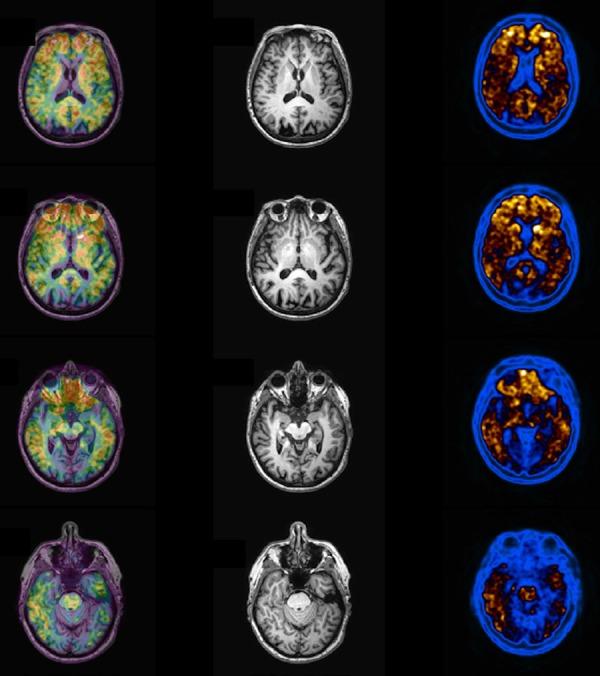

阿尔茨海默病的多模态成像方法。第二部分:氢质子磁共振波谱、氟代脱氧葡萄糖正电子发射断层显像和淀粉样蛋白正电子发射断层显像

Multimodality Imaging Approaches in Alzheimer's disease. Part II: 1H MR spectroscopy, FDG PET and Amyloid PET.

In this Part II review, as a complement to the Part I published in this supplement, the authors cover the imaging techniques that evaluates the Alzheimer's disease according to the different metabolic and molecular profiles. In this section MR spectroscopy, FDG-PET and amyloid PET are deeply discussed.

摘要

在本第二部分综述中,作为对本增刊第一部分的补充,作者介绍了根据不同代谢和分子特征评估阿尔茨海默病的成像技术。在本节中,将深入讨论磁共振波谱、氟代脱氧葡萄糖正电子发射断层显像(FDG-PET)和淀粉样蛋白正电子发射断层显像(amyloid PET)。